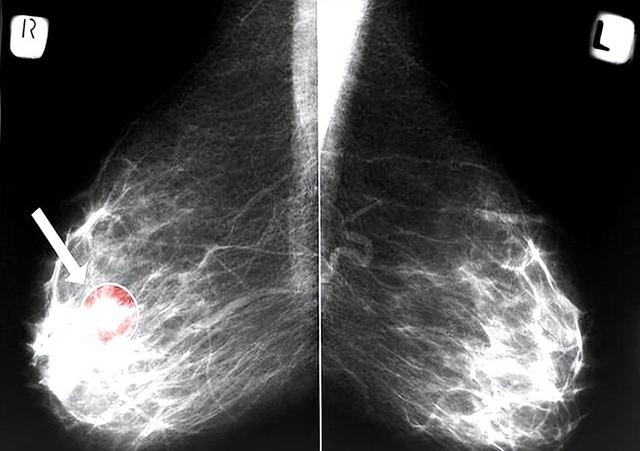

研究发现每周喝七次奶的群体肝癌风险升12%、乳腺癌升17%,但仔细看数据就会发现这些人都存在乳糖代谢障碍。